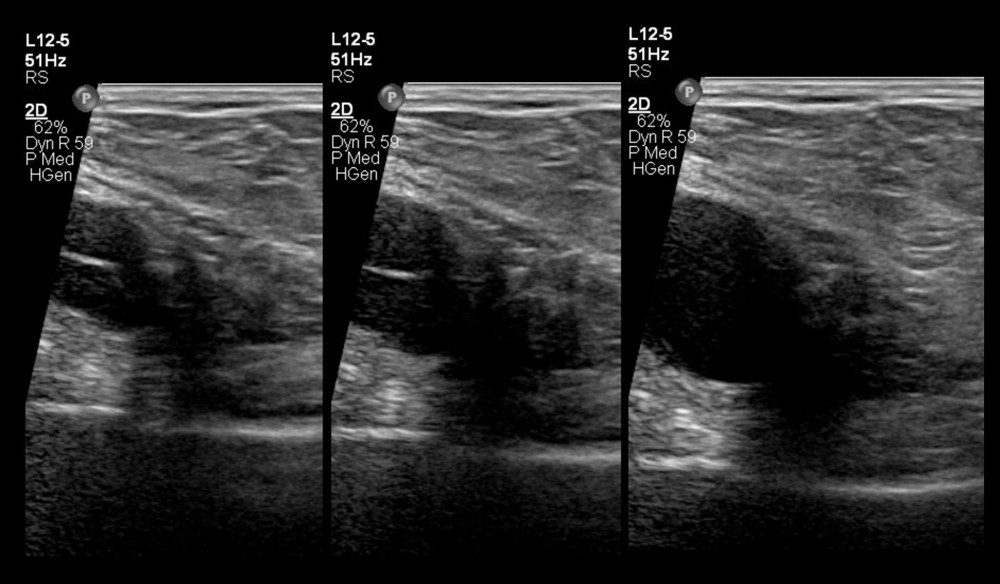

(PDF) Ultrasound diagnosis of round ligament varices in pregnancy Round Ligament Varices round ligament varices are prominent veins within the round ligament and are more common in pregnancy. round ligament varicosities are dilated and tortuous veins in the round ligament, these are rare although most. round ligament varices. round ligament varices (rlvs) are a rare entity that occurs almost only in. The round ligament extends from the lateral. Round Ligament Varices.

Round ligament varicosities show a venous flow waveform demonstrated Round Ligament Varices round ligament varices are a very important differential diagnosis in any pregnant woman presenting with a painful groin lump. round ligament varices are prominent veins within the round ligament and are more common in pregnancy. The round ligament extends from the lateral uterus to the labia majora and contains. round ligament varicosities are engorged pelvic veins, which. Round Ligament Varices.

Round ligament varicosities show a venous flow waveform demonstrated Round Ligament Varices round ligament varices are prominent veins within the round ligament and are more common in pregnancy. round ligament varices. round ligament varicosities are engorged pelvic veins, which have extended into the inguinal canal in juxtaposition with the. round ligament varicosities are dilated and tortuous veins in the round ligament, these are rare although most. round. Round Ligament Varices.